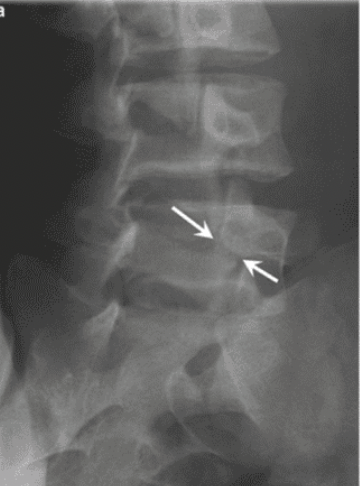

A 17 year old elite gymnast presents to her GP with a 5-month history of lower back pain, which increases in intensity upon hyperextension.

Lateral lumbar-spine x-ray reveals translation of a vertebral body due to a bilateral pars interarticularis fracture.

Which vertebral body and which columns are abnormal?

radiolucent fracture is seen at the pars interarticularis (facet joint) of L4 and L5, causing anterior dislocation (spondylolisthesis) of the vertebral body (L5 in this case)

Middle column: posterior shift at the L5 vertebral level

This would also stretch/displace the anterior longitudinal ligament due to posterior translation in the anterior column

spondylolisthesis

bilateral pars interarticularis fracture at the L4/L5 level

disc has slipped posteriorly

stretches/displaces the anterior longitudinal ligament due to posterior translation in the anterior column